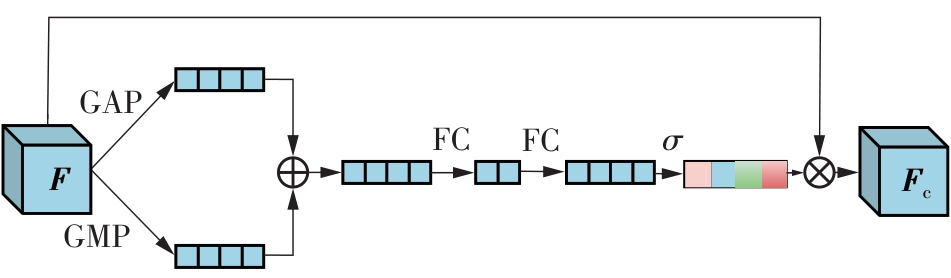

乳腺癌是全球女性最常见的恶性肿瘤之一,准确的病变分割对于乳腺癌的早期诊断与治疗具有重要意义。然而,由于病变形态的多样性以及超声成像机制的复杂性,现有基于深度学习的乳腺超声图像病变分割方法在分割准确性方面仍面临巨大挑战。为进一步提升乳腺超声图像中病变区域的分割精度,该文基于经典U-Net架构,提出了一种新型乳腺超声图像病变分割网络(CWSASKM-BBAM-Net)。首先,在网络中引入逐通道空间自适应选择核卷积模块(CWSASKM),根据不同通道的语义特征为每个空间位置自适应选择感受野大小,以增强多尺度信息的建模能力;然后,引入双向边界感知机制(BBAM),通过融合正向与反向注意力,对目标显著区域及其边界进行协同建模,同时逐步提升对非显著区域与病变区域的区分能力,以进一步强化边界信息的表达;最后,在3组公开乳腺超声图像数据集(BUSI、UDIAT和STU)上开展分割实验。结果表明:该方法在数据集BUSI上的杰卡德指数、精确率、召回率和Dice相似系数分别为71.97%、82.85%、81.40%和80.44%,较次优方法分别提升1.69、1.05、1.28和1.84个百分点;在数据集UDIAT上,这4项指标分别达到78.14%、88.31%、86.73%和86.10%,较次优方法分别提升了2.75、2.04、0.56和2.01个百分点;在外部数据集STU上,该方法也取得了优于其他方法的整体表现。实验结果表明,CWSASKM-BBAM-Net在乳腺超声图像分割任务中展现出更优的整体性能。